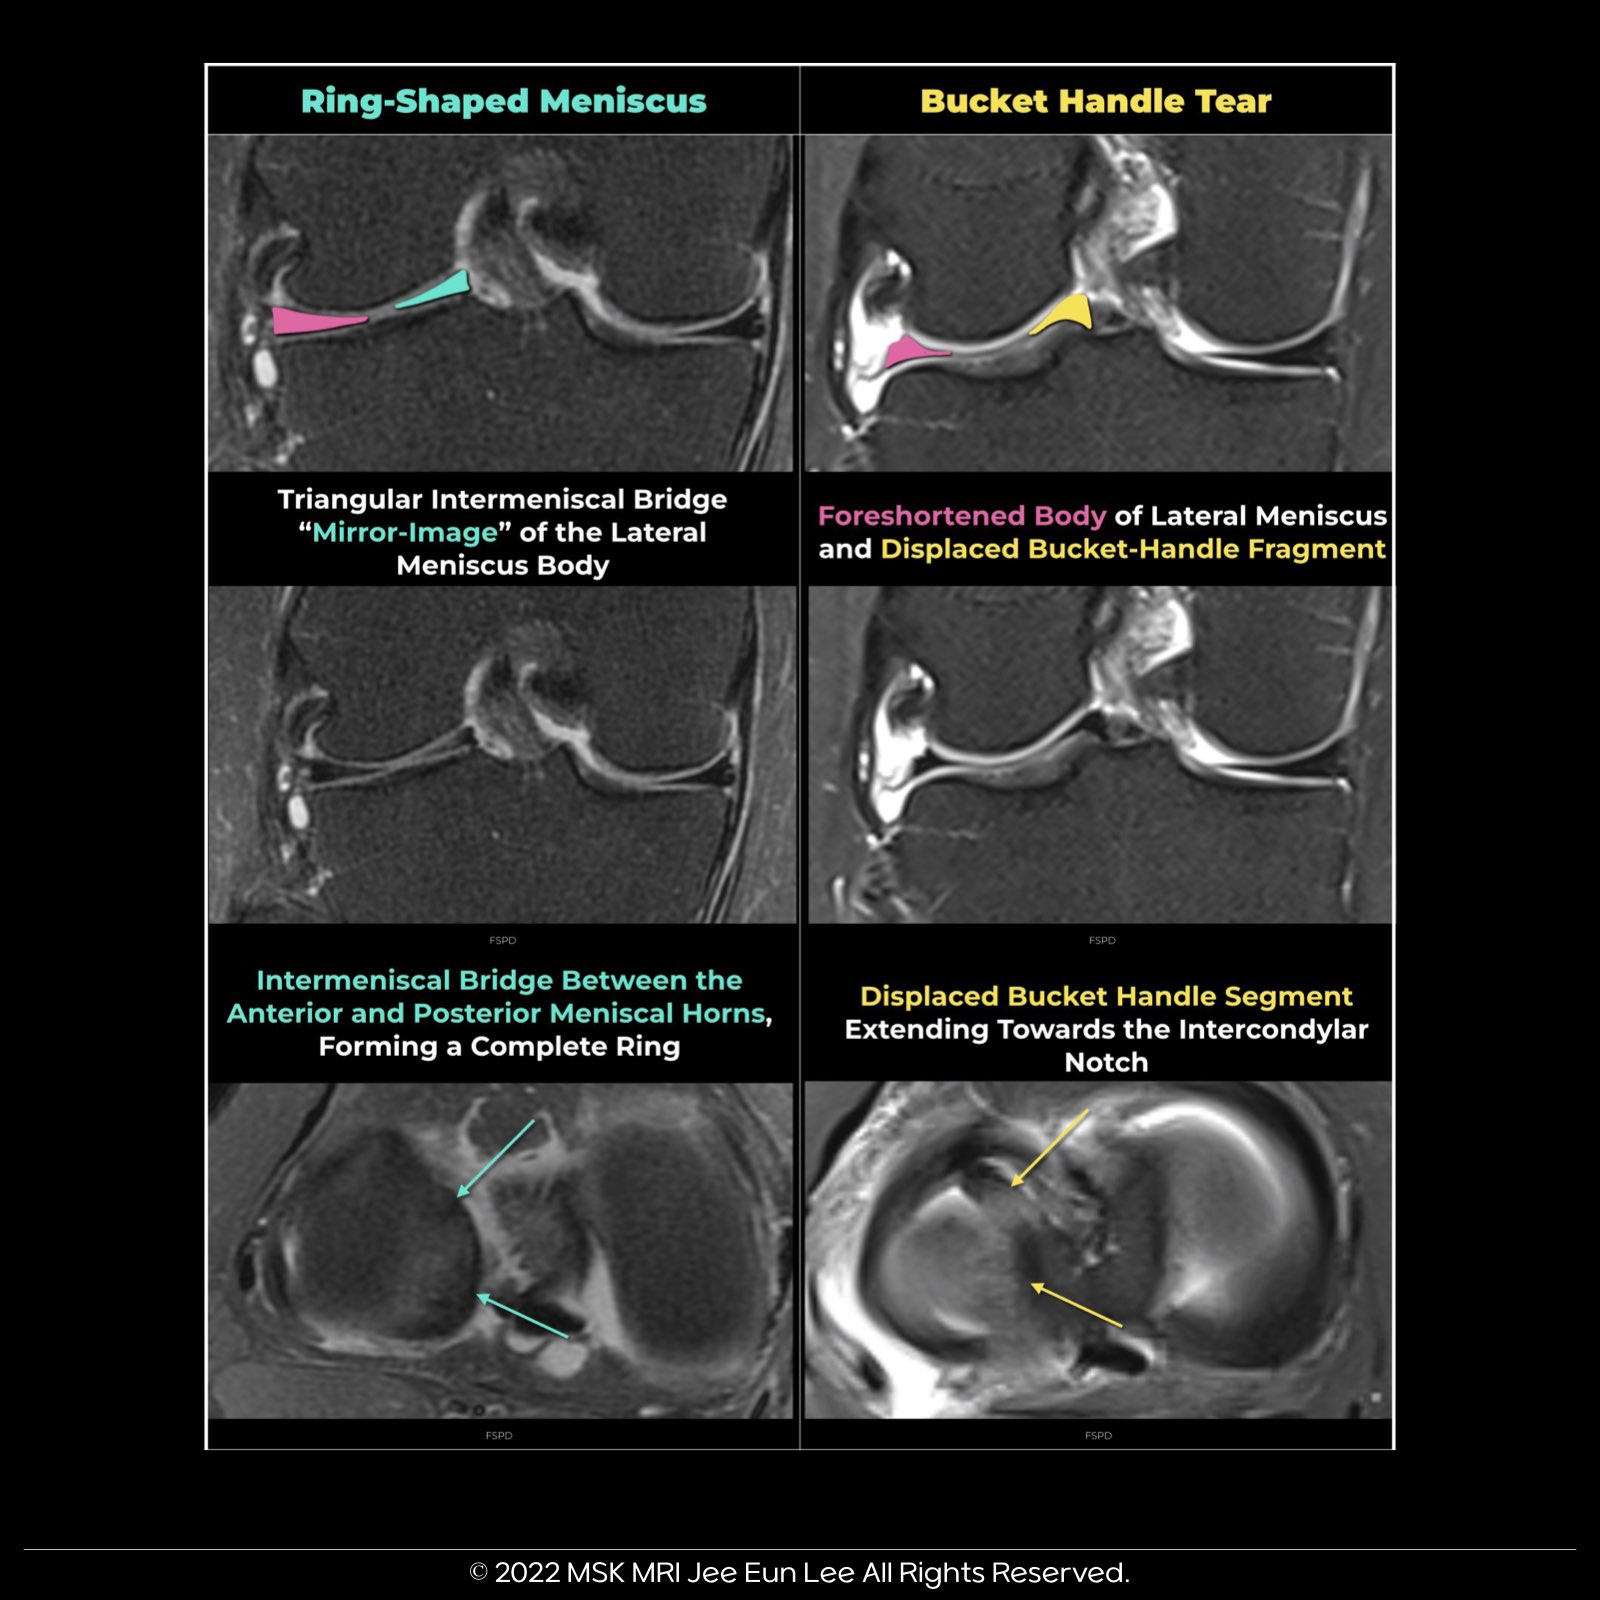

4️⃣Ring-shaped meniscus:

Connects between the roots, resembling a medially displaced meniscal fragment without an identifiable donor site in imaging.